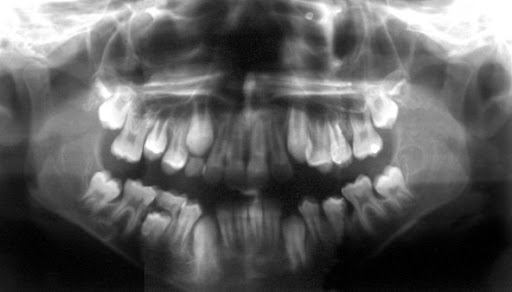

Panorâmicas

A técnica radiográfica panorâmica tem uma posição de grande importância como auxiliar de diagnóstico, sendo que suas vantagens superam as desvantagens.(10)

É indicada quando se deseja ampla visão da maxila e mandíbula para análise das dimensões e forma anatômicas, ou quando há suspeita de processos degenerativos ou outras patologias ósseas porém, é contra-indicada para inspeção e interpretação funcional da ATM, pois durante este

exame o paciente morde um artefato acrílico.

Suas principais vantagens são: as imagens dos dois ramos ascendentes e côndilos podem ser vistas simultaneamente. A técnica é relativamente fácil e a aparelhagem de fácil aquisição e os programas mais modernos têm programas específicos para ATM .(15)

Esta técnica também tem melhor aceitação por todos os grupos de pacientes, principalmente as crianças, devido às facilidades oferecidas.(10)

Entre as desvantagens estão: sobreposição de imagens e simulação de patologias inexistentes15. Tempo de exposição longo, o qual pode propiciar movimentação do paciente durante a realização da técnica. (10)

O relacionamento do côndilo na fossa mandibular é distorcido porque a mandíbula é protruída quando é feita a exposição5.